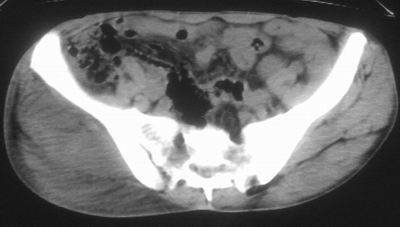

标题: CT16837:M63Y,右臀部巨大软组织包块 [打印本页]

患者,男,63岁,自诉3个月前发现右臀部包块,触及疼痛,治疗后缩小。前天突然增大。无高热病史。

考虑-----右臀大肌,臀中肌---感染性病变可能性大。

恶性软组织肿瘤可能性不大

病灶内部可见出血,首先考虑急性出血性病变.血肿?

给个骨窗,判断一下肿块是否与髂骨有关,肿块内出血是肯定的,至于是感染形成的脓肿还是起源于肌肉或纤维组织的肉瘤则难以确定,不过从影像上看,包膜完整,且环形增厚,病灶下部见斑片状底密度坏死,个人倾向感染可能性大

肌间隙明显混浊,三个月前治疗有缩小,支持考虑臀大肌下脓肿伴出血,肿瘤如果出现瘤内出血的话瘤外边界应该较清楚,现在表现为一种恶性征像,但骨质无明显异常,且臀小肌边界清楚,不符合恶性表现.